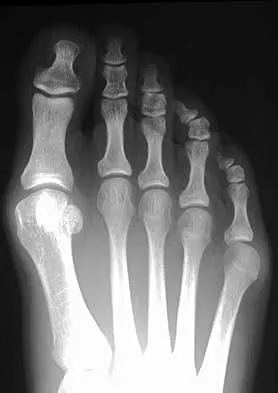

A 19-year-old woman has had a painful prominence on the lateral border of her fifth metatarsal head since she was a young girl. Nonsurgical management, including the use of a wide toe box shoe, has failed to provide relief. Examination reveals a callus over the lateral prominence and on the plantar portion as well. A clinical photograph and a radiograph are shown in Figures 34a and 34b. Treatment should consist of

Explanation

The type of deformity described is a type 2 bunionette. There is often a congenital component to this deformity. The bowing of the fifth shaft differentiates a large intermetatarsal angle from a type 3 deformity. A distal chevron osteotomy corrects 1 degree in the intermetatarsal angle for every 1-mm shift. Because of limitations in the width of the fifth metatarsal neck, the allowable shift is generally 3 to 4 mm. This shift will not compensate for the large intermetatarsal angle. The floating osteotomy has a high rate of delayed union/nonunion and a low satisfaction rate. Metatarsal head excision has a high complication rate, including severe shortening, transfer metatarsalgia, stiffness, and pain. A more proximal procedure is necessary to correct the large intermetatarsal angle and the lateral bowing. The osteotomy of choice is a diaphyseal shaft osteotomy. Because this patient has a plantar callosity and a lateral callosity, the osteotomy is angled superiorly to elevate the fifth shaft with the shift, eliminating overload of the plantar metatarsal head and subsequent callus formation. Shereff MJ, Yang QM, Kummer FJ, Frey CC, Greenidge N: Vascular anatomy of the fifth metatarsal. Foot Ankle 1991;11:350-353. Coughlin MJ: Treatment of bunionette deformity with longitudinal diaphyseal osteotomy with distal soft tissue repair. Foot Ankle 1991;11:195-203.